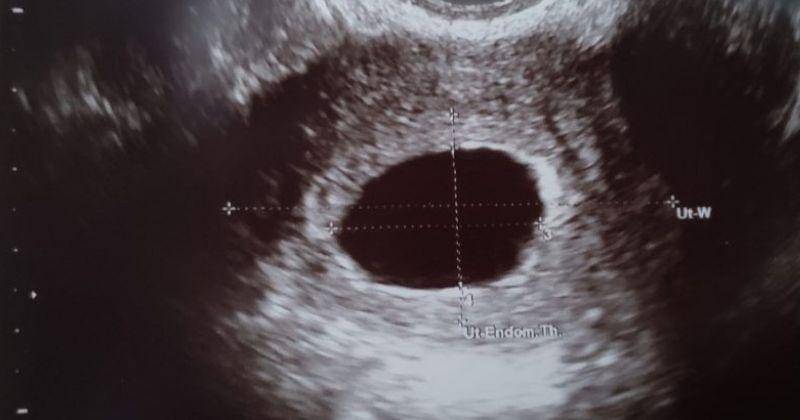

Kehamilan kosong, yang juga disebut dengan blighted ovum, merupakan keguguran yang terjadi ketika sel telur yang telah dibuahi telah tertanam ke dalam rahim tetapi tidak berkembang menjadi embrio.

Embrio akan berhenti tumbuh, tetapi kantungnya (tempat embrio berkembang) terus tumbuh. Plasenta dan kantung kehamilan yang kosong ini tetap melepaskan hormon kehamilan, bahkan tanpa kehadiran embrio.